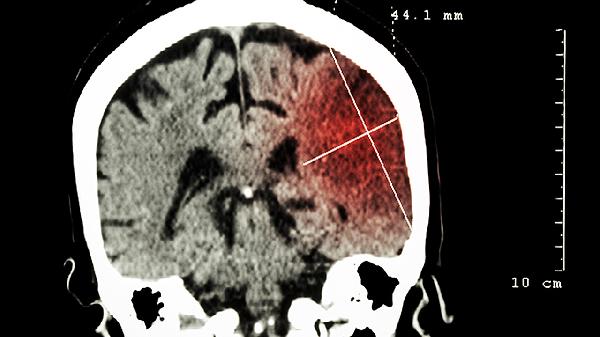

脑瘤初期CT通常能发现,但检出率与肿瘤大小、位置及类型有关。脑瘤初期可能表现为脑组织密度异常、占位效应或钙化等影像学特征,常见类型包括胶质瘤、脑膜瘤、垂体瘤等。建议结合临床症状及进一步检查明确诊断。

CT检查对直径超过5毫米的脑瘤具有较高检出率,尤其是伴有出血或钙化的肿瘤。高密度病灶如脑膜瘤在平扫CT中较易识别,低密度病灶如部分胶质瘤需增强扫描提高检出率。脑干、小脑等后颅窝区域因骨骼伪影干扰可能影响早期病灶显示。对于微小的垂体瘤或听神经瘤,MRI检查敏感性更高。